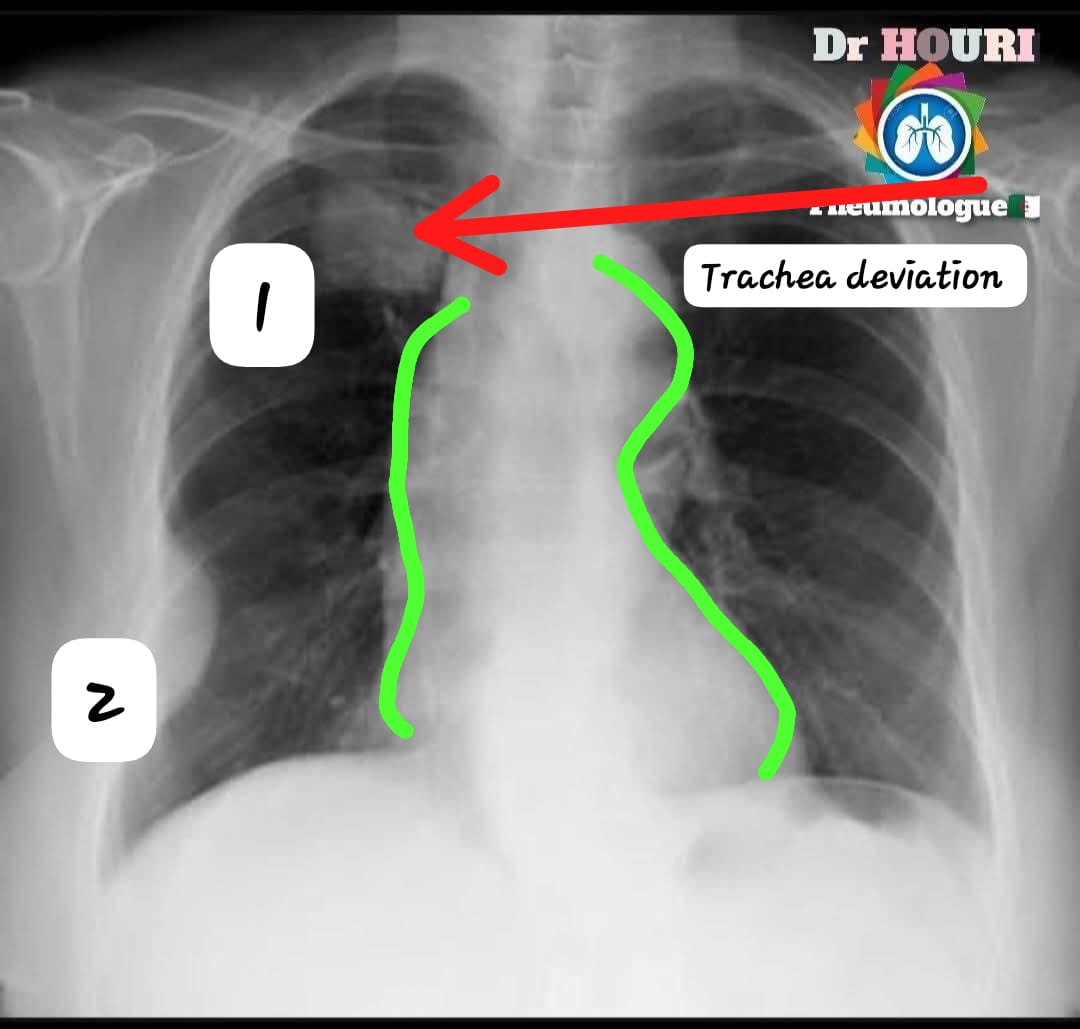

C.Alberto Ortega अहिरावण [1]There is upper mass at the upper right quadrat lobe + hx of smoking 🚬 + weight loss [Green]midesternal widening +[green]arbitration of heart boundaries +trachea deviation towards theRight sided Dx- pulmonary 🫁 Carcinoma/ Mass 2/2 To carcinogenic substance exposure Ddx2:PE

<a href="/albertoortegana/">C.Alberto Ortega</a> <a href="/dr_manish_ydv/">अहिरावण</a> [1]There is upper mass at the upper right quadrat lobe + hx of smoking 🚬 + weight loss

[Green]midesternal widening +[green]arbitration of heart boundaries +trachea deviation towards theRight sided

Dx- pulmonary 🫁 Carcinoma/ Mass 2/2 To carcinogenic substance exposure

Ddx2:PE